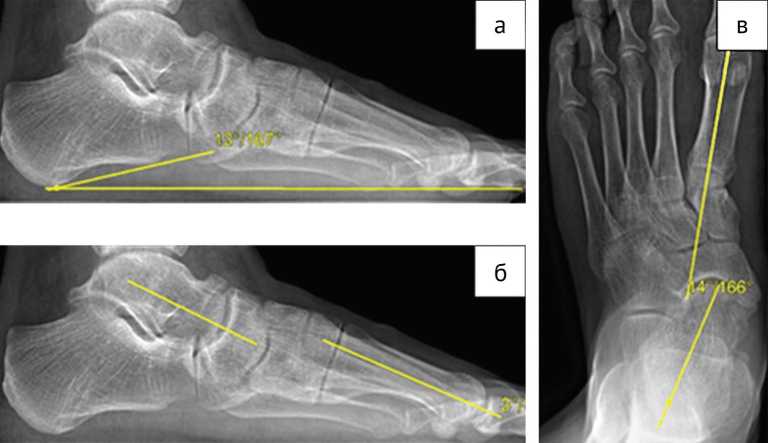

Каждому пациенту, участвующему в исследовании, при госпитализации и через год после операции проводили рентгенологическое исследование стопы с нагрузкой в двух проекциях (прямой и боковой). На рентгенологических снимках в боковой проекции оценивали пяточно-подошвенный угол между пяточным бугром (рис. 1, а) и поперечной плоскостью, таранно-первоплюсневый угол между осью таранной кости и осью первой плюсневой кости (рис. 1, б). На прямой проекции измеряли угол между осью таранной и первой плюсневой костями (рис. 1, в). На основании измерений, проведенных до операции, оценивали степень снижения продольного свода, отведения переднего отдела стопы и вальгусную деформацию стопы, а также корригирующую способность предлагаемого метода. На следующий день после операции рентгенографическое исследование проводили без нагрузки на стопу, оценивали уровень остеотомии, положение трансплантата и металлофиксатора. Через год после хирургического лечения на контрольных рентгенограммах с нагрузкой на стопу измеряли степень коррекции деформации и ее сохранение в течение года, анализировали консолидацию области остеотомии, положение трансплантата и металлофиксатора, деформирующий остеоартроз окружающих суставов.

Рис. 1. Рентгенограммы стопы с нагрузкой: а — боковая проекция, угол между пяточной костью и поперечной поверхностью;

б — боковая проекция, угол между осью таранной кости и первой плюсневой;

в — прямая проекция, угол между осью таранной кости и первой плюсневой

Клинический пример группы сравнения

Пациент 1989 года рождения поступил в ННИИТО им. Я.Л. Цивьяна с жалобами на деформацию левой стопы, болевой синдром при нагрузке в среднем отделе стопы, а также болезненность при ношении обуви. Согласно анамнезу, деформацию обеих стоп больной отмечал в течение длительного времени. Пациента наблюдал травматолог в поликлинике по месту жительства, однако консервативная терапия не привела к значимому улучшению, происходило прогрессирование деформации. На основании клинического осмотра, данных анамнеза и рентгенологического исследования установлен диагноз: плосковальгусная деформация стоп 2-й степени слева, Hallux Valgus bilateralis 1–2-й степени. Пациенту выполнено предоперационное планирование и хирургическая коррекция деформации классическим методом остеотомии Evans. По результатам рентгенографии голеностопного сустава до операции получены следующие параметры: пяточно-подошвенный угол — 13°, таранно-первоплюсневый угол в прямой проекции — 14°, в боковой проекции — 3° (рис. 1). МСКТ-исследование до хирургического вмешательства не проводили. На следующий день после операции выполнили МСКТ стопы, которая выявила наличие объединённой передней и средней суставных фасет подтаранного сустава, повреждённых в ходе оперативного вмешательства (рис. 4).

Через год после хирургического лечения проведено контрольное рентгенологическое исследование голеностопного сустава с нагрузкой в двух проекциях. Получены следующие показатели: пяточно-подошвенный угол — 21°, таранно-плюсневый угол в прямой проекции — 3°, в боковой проекции — 4°. Выполнено анкетирование по шкале AOFAS, которое продемонстрировало улучшение показателей с 53 баллов до операции до 87 баллов после хирургического лечения.